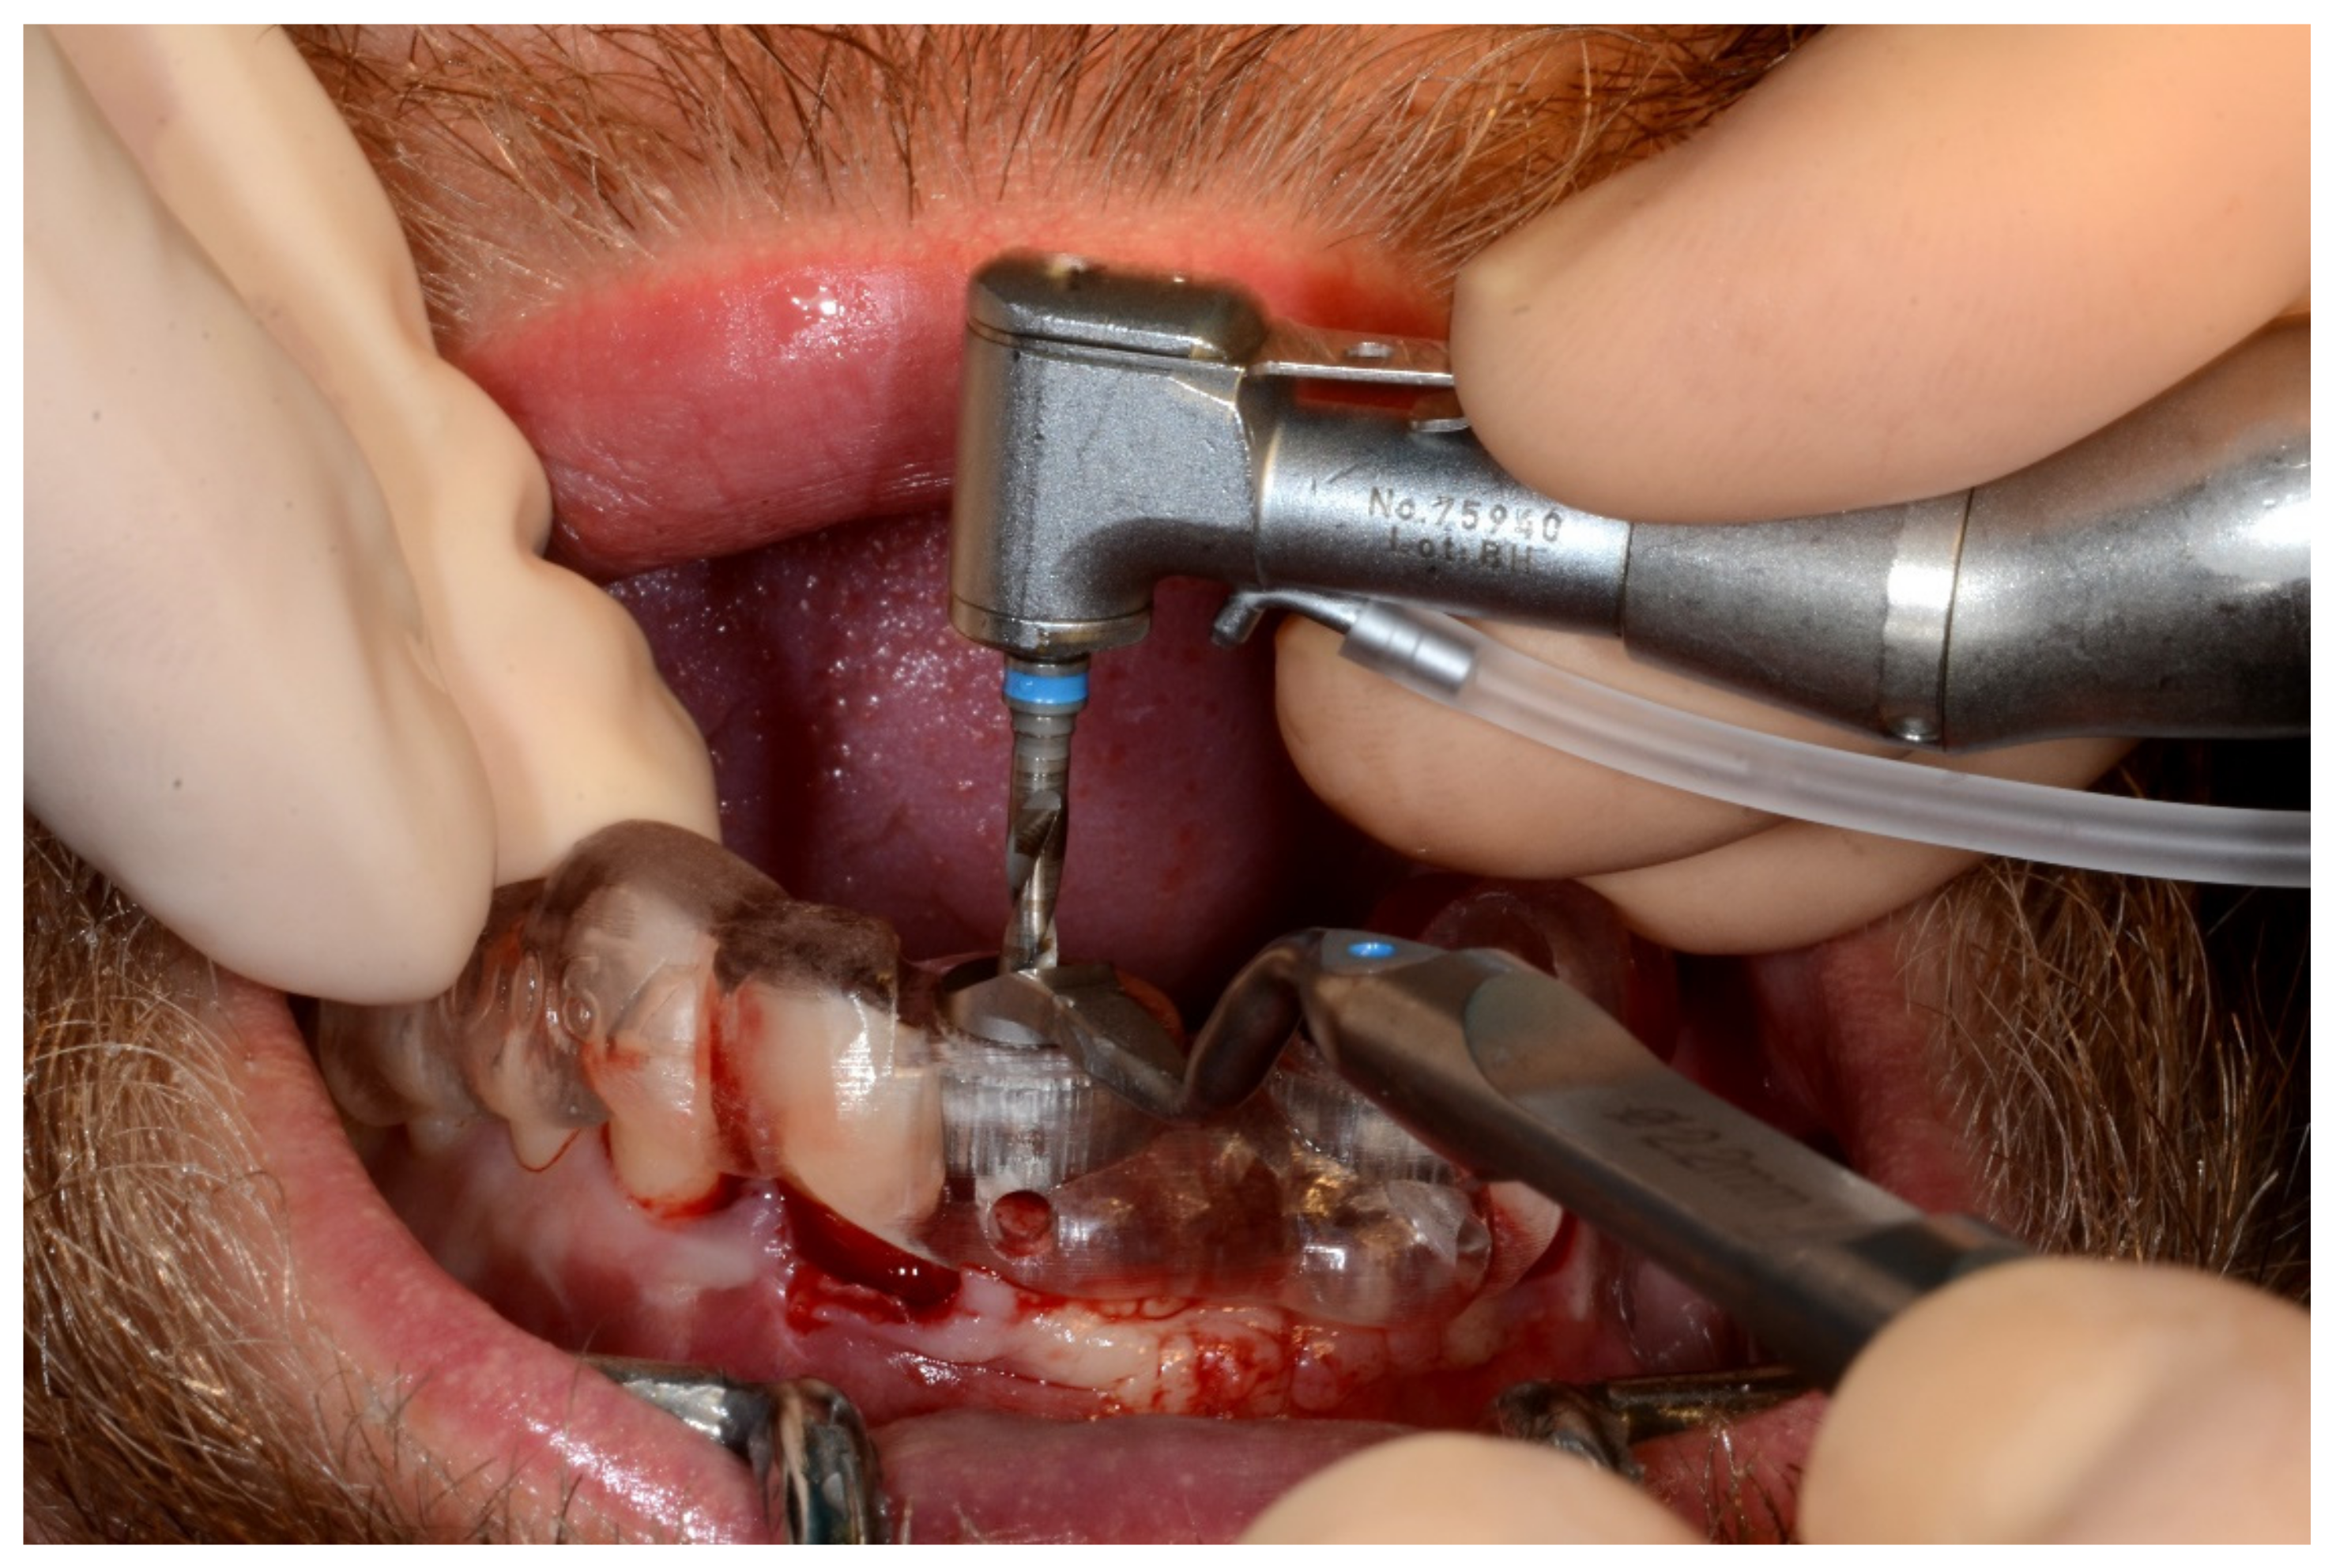

6.1.4. Intra-Operative Documentation: